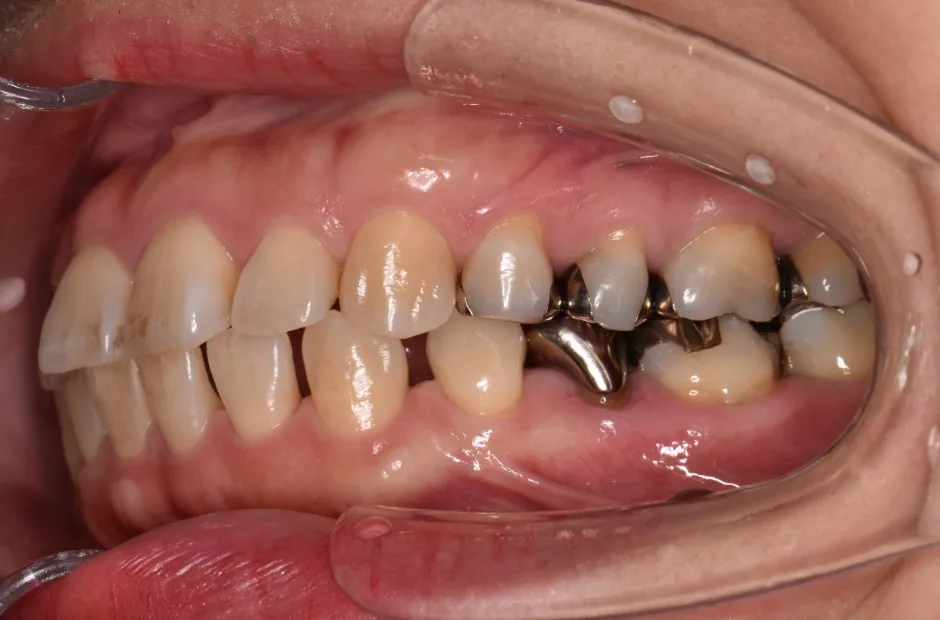

叢生

| 診断名・主訴 | 叢生 |

|---|---|

| 年齢・性別 | 43歳・女性 |

| 治療期間・回数 | 2年7か月 27回 |

| 治療に用いた主な装置 | 舌側矯正 |

| 抜歯部位 | 両顎4,4 |

| 治療費 | 100万円(税抜) |

| リスク・副作用 | 装置による違和感・疼痛・歯肉退縮・歯根吸収・虫歯のリスクなど |

治療前